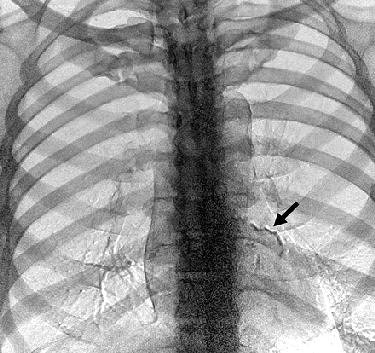

| Sixty-seven-year-old man who underwent dual-energy subtraction radiography for preoperative evaluation. Above, conventional posteroanterior chest digital radiograph is unremarkable. Below, subtracted bone image shows evidence of linear calcification (arrow) in distribution of left coronary artery, which is consistent with coronary artery calcification. Gilkeson RC, Novak RD, Sachs P, "Digital Radiography with Dual-Energy Subtraction: Improved Evaluation of Cardiac Calcification," (AJR 2004;183: 1233-1238). |

![]() |

Patient x-rays were taken at 120 kVp and 60 kVp, enabling the routine generation of three images after postprocessing: a standard 120 kVp image, a subtracted soft-tissue image, and a subtracted bone image. In patients with suspected cardiac calcification on the low-energy bone image, the radiologist was asked to rate visualization of coronary calcification on that image compared to the standard posteroanterior and lateral radiographs.

"Of the 33 patients with suspected cardiac calcification on dual-energy digital radiography, all 33 had confirmed CT evidence of cardiac calcification," the authors wrote. "Suspected coronary artery calcification on dual-energy digital radiography was also confirmed in all 33 patients on CT, and valvular and myocardial calcifications were proven in three of the 33 patients."

The comparison with CT images also confirmed a limitation of the present dual-energy techniques, which is that left and right coronary artery calcifications were not equally visible on radiography even though all patients showed bilateral calcification on CT.